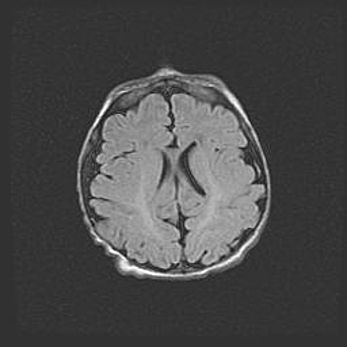

Лейкомаляция с кистозно-глиозной дегенерацией головного мозга.

Возраст: 2 месяца 25 дней

Вес: 6400 г

Окружность головы: 40 см

Срок гестации: 41 неделя

Лейкомаляцию относят к ишемически-гипоксическим повреждениям головного мозга, диагностируемым у новорожденных. При лейкомаляции в головном мозге обнаруживают очаги некроза, возникшие после тяжелой гипоксии и нарушения кровотока. В процессе морфогенеза очаги проходят три стадии: 1) развития некроза, 2) резорбции и 3) формирования глиозного рубца или кисты. Перивентрикулярная лейкомаляция (ПЛ) встречается примерно в 12% случаев среди новорожденных, обычно – у недоношенных детей, причем, частота ее зависит от массы, с которой младенец появился на свет. Наибольшее число малышей страдает лейкомаляцией, если масса при рождении 1500-2500 г.